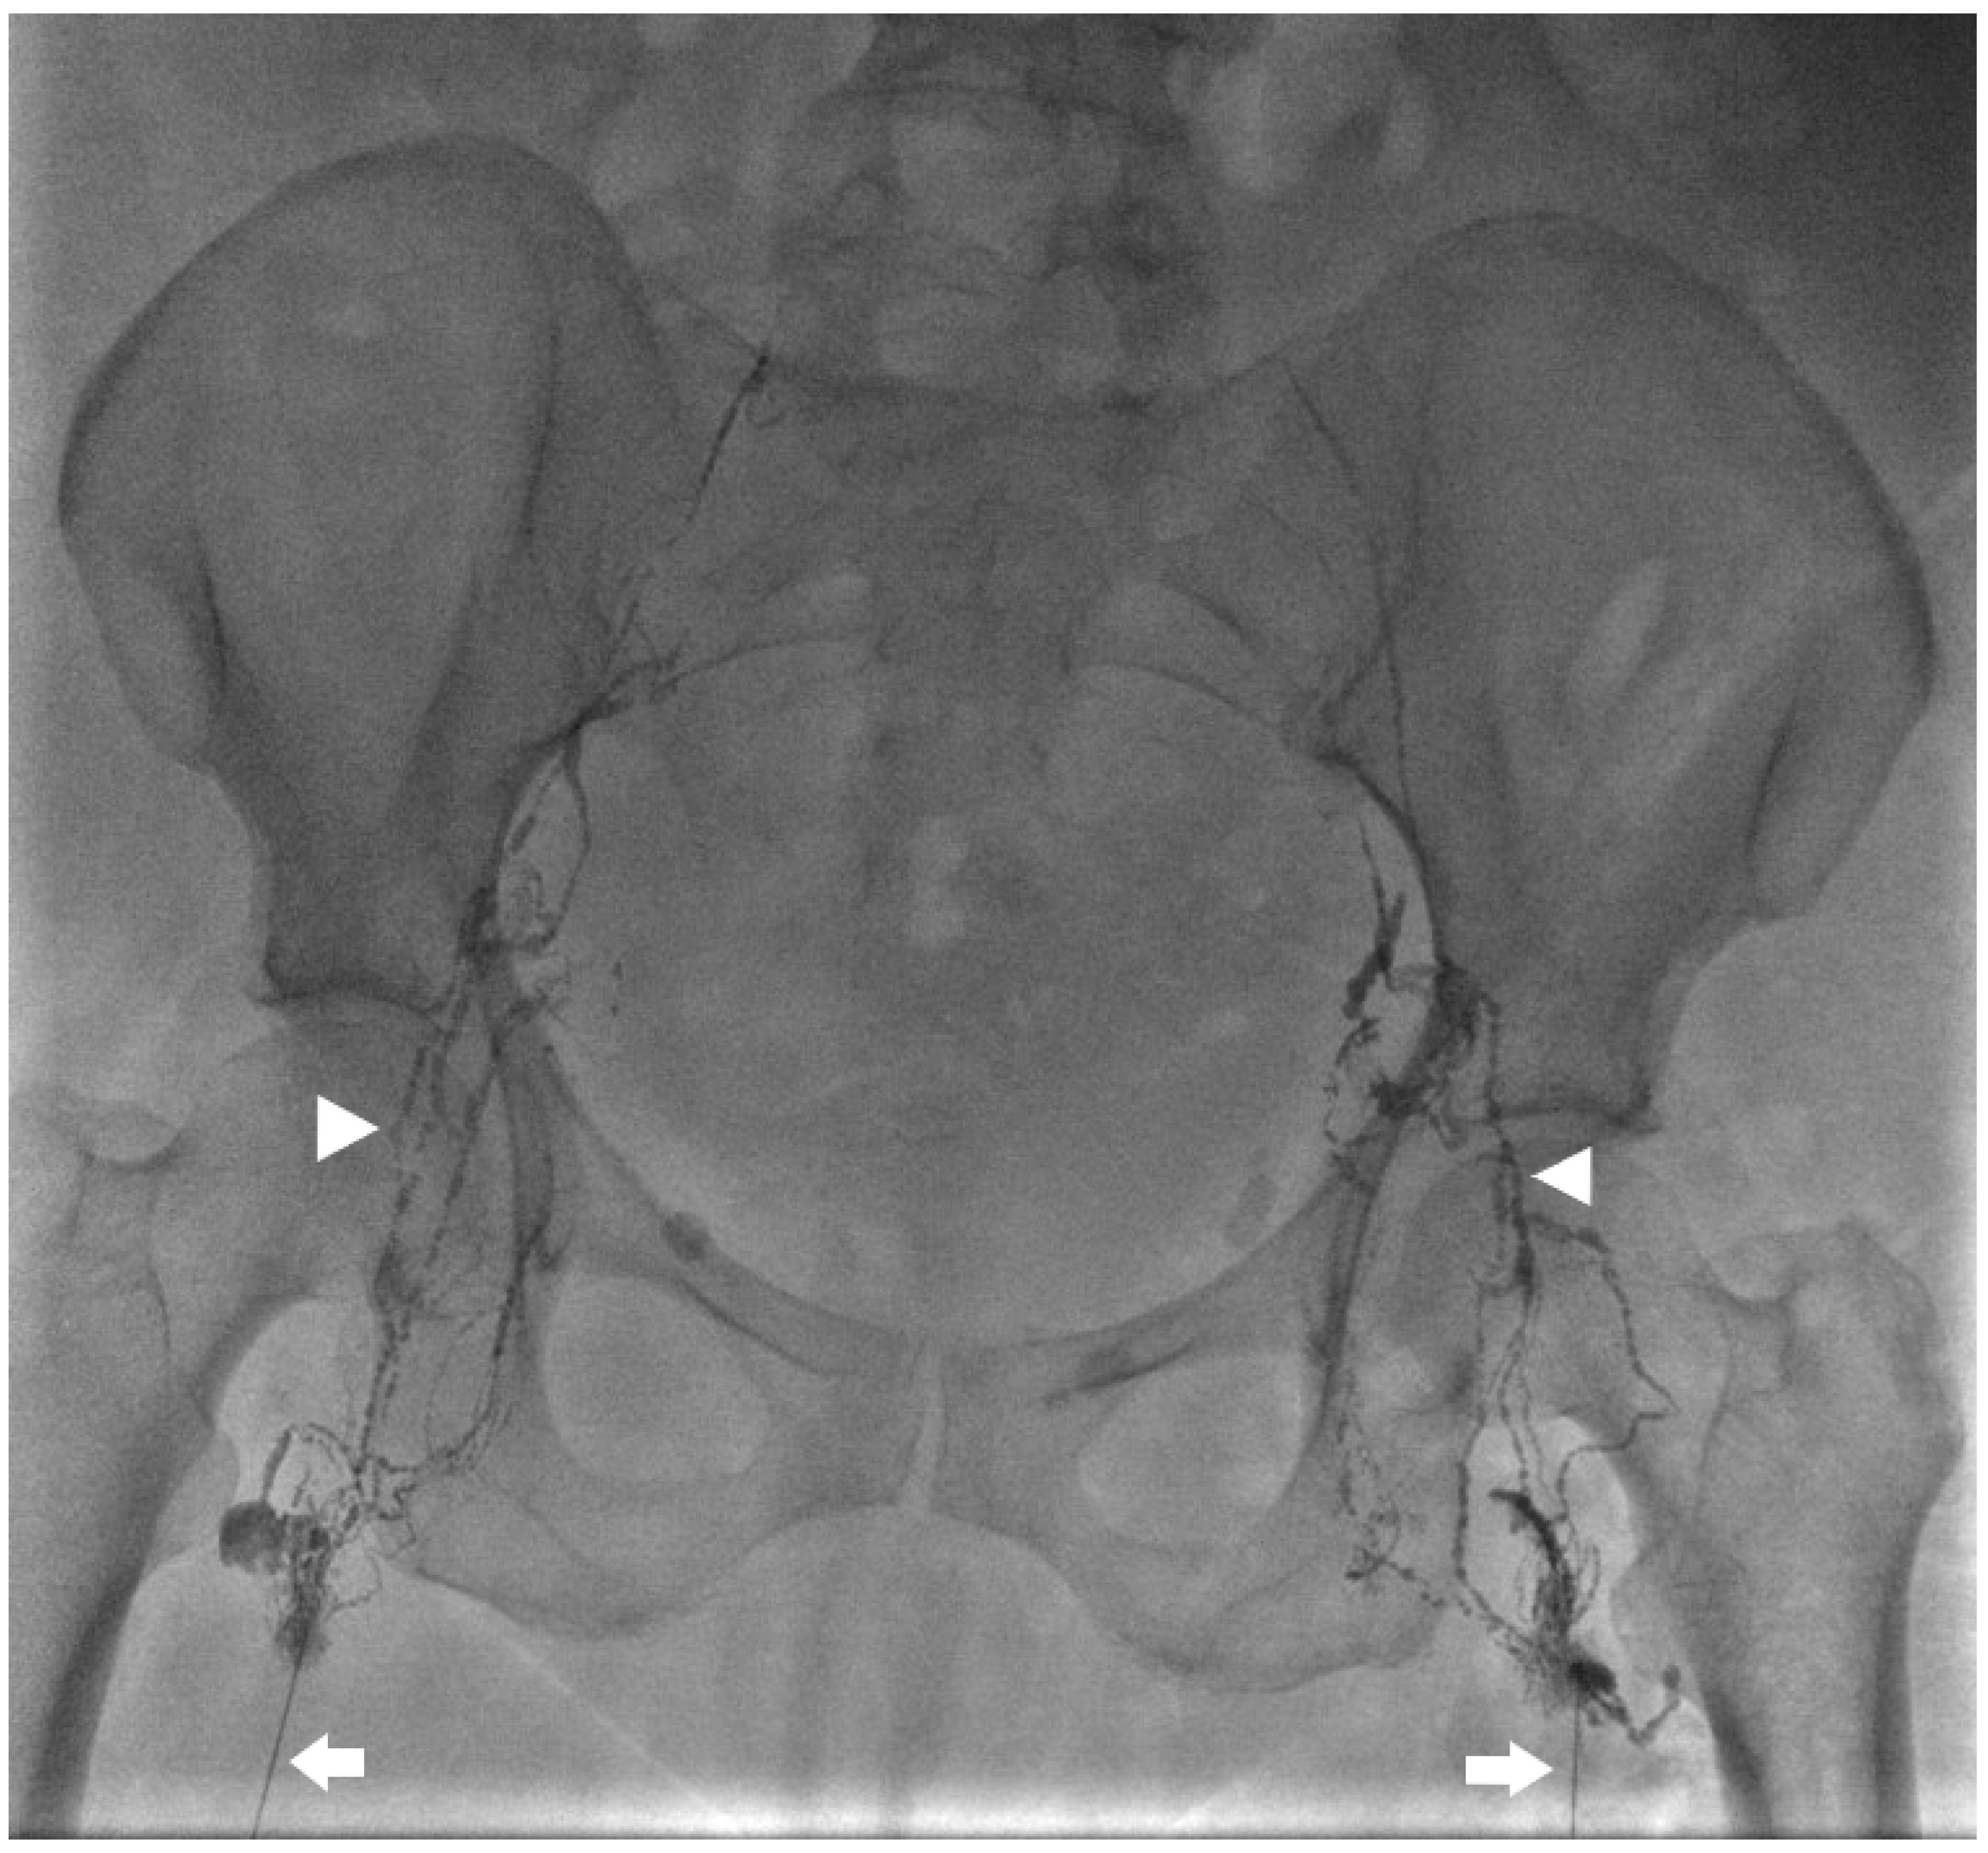

Kaminski et al. compared lymphangiography only versus lymphangiography and embolization. The median amount of iodized oil (lipidol) used was 12 mL (range 8–20 mL) with 20 mL used in all cases of lymphangiography only. Embolization of the target lymph vessel was performed with coils and/or liquid embolics (Histoacryl) diluted with ratio 1:1–1:5. Coils were used in the embolization of large lymph vessels to prevent distal migration of glue to the venous system (Figure 3 and Figure 4). Glue-only embolization was performed in peripheral lymphatics with no risk of glue migration or lymph node embolization. When embolization was not feasible, interstitial lymph node embolization was performed. Dietary restriction with Medium Chain Triglyceride supplement was prescribed for 2–3 days post-procedure. Embolization achieved 26/28 (92.9%) and 11/12 (91.7%) clinical success in traumatic and non-traumatic thoracic chylous effusion, respectively; lymphangiography only achieved 1/2 (50.0%) and 1/6 (16.7%) in traumatic and non-traumatic thoracic chylous effusion, respectively. Clinical success in combined abdominothoracic chylous effusion was achieved in 2/3 (66.7%) and 0/5 (0.0%) of embolization and lymphangiography only patients, respectively. Overall success of thoracic intervention was 39/48 (81.3%) with a significant difference between traumatic and non-traumatic groups. Complications were seen after lymphatic embolization in 5 patients with one grade 1, two grade 2, one grade 3, and one grade 4 as follows: pulmonary glue migration, upper extremity vein thrombosis, edematous pancreatitis, bleeding from branch of left hepatic artery, biliary peritonitis [22].

Figure 3.

Spot image from an intra-nodal lymphangiogram for a 59-year-old patient with traumatic chylothorax after esophagectomy. Bilateral 25 G needles (arrows) are used to inject lipiodol into the inguinal lymph nodes and up the lymphatic vessels (arrow heads).